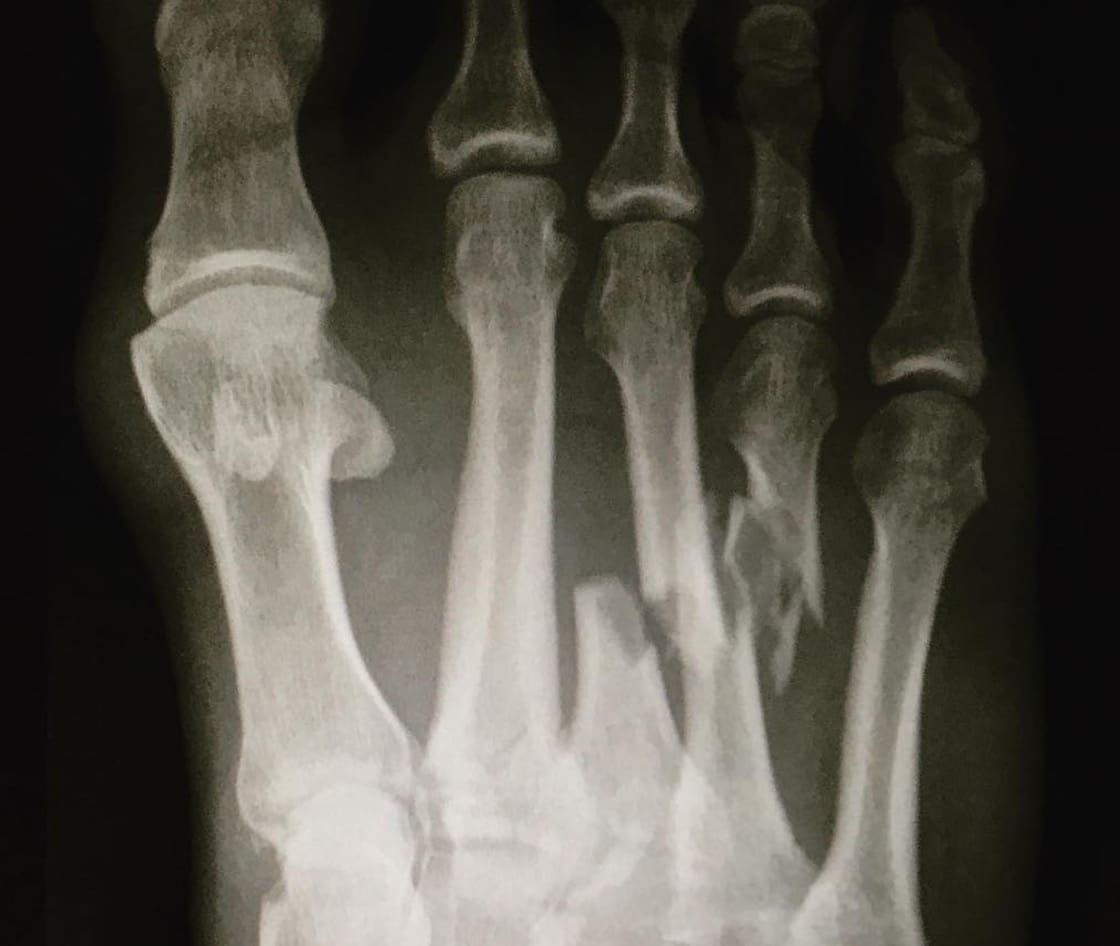

It’s not often that Kelly Slater crashes but when he does– he breaks two of his toes in half.

That’s what happened this morning while Slater was ‘freesurfing’ at ‘Boneyards’ in preparation for the prestigious Corona J-Bay Open taking place this week.

In a video posted to Instagram by the World Surf League, Slater is seen in visible pain while going on to say that he won’t be able to compete at the J-Bay event in addition to the Billabong Pro Tahiti set to take place later in August. Slater had previously hinted that this may be his final year on tour. He is currently ranked 18th on the Jeep WSL leaderboard.